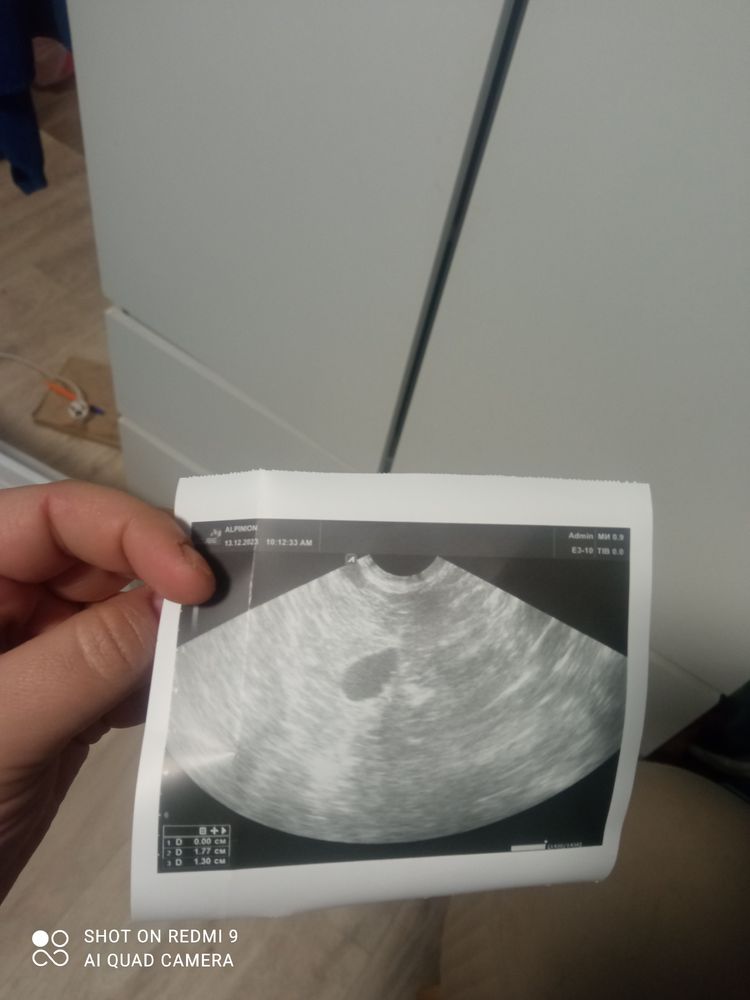

Что это подскажите плиз

Ну, если вы про пятно, то это яйцеклетка а не жидкость 😁

Людмила, я про пятно, мне сказали это жидкость, это не беременность.?

Диана Бояркова, попробуйте в динамике сделать. Авось повезёт Но скорей всего это просто железа эндометрия попалась

Людмила, какая яицеклетка😂 🤦‍♀️ больше похожа на плодное яйцо🤷‍♀️

Ольчик, ох блин 🤣🤣 не туда меня понесло на ночь глядя. Но всё же, хгч 0.2. Надо динамику посмотреть просто

Ольчик, точно ? Я посмотрела примеры по фото Это беременность 2 неделя Тесты полосят.. Но кровь, и гинеколог говорит что только это жидкость

Диана Бояркова, сдайте еще раз хгч и если он отрицательный, то это жидкость. Кровь на хгч точнее тестов